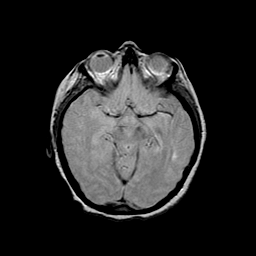

Basal Ganglia Calcification: proton density-weighted MR -- Slice #7

[Home][Help][Clinical] Slice 7